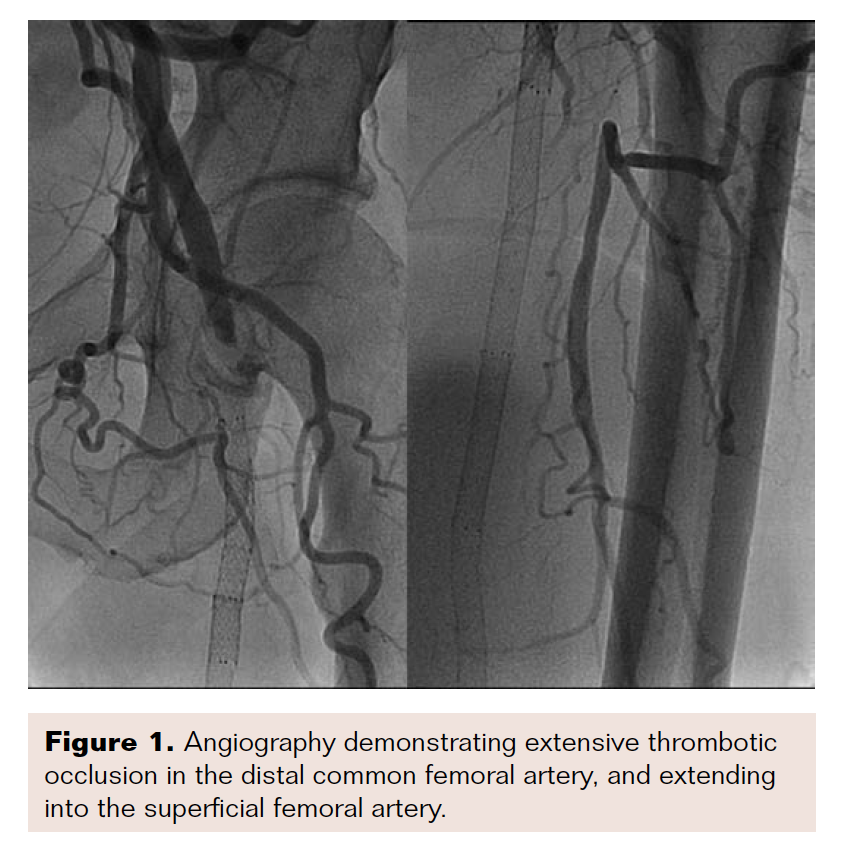

A 50-year-old man with a history of PAD, failed femoral-popliteal bypass grafting, and prior superficial femoral artery (SFA) intervention presented to the emergency department with Rutherford class IIa symptoms that had persisted for one week. Doppler ultrasound showed a possible clot in the left common femoral artery, with poor run-off.

Angiogram revealed acute thrombotic occlusion of the left distal common femoral artery and SFA, with reconstitution at the tibioperoneal trunk (Figures 1-2). Initial balloon angioplasty was performed at the distal common femoral artery and proximal SFA. A 50 cm Ekos catheter was placed from the common femoral artery to the popliteal artery on the left side.